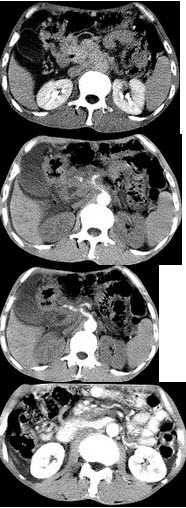

女,45岁,急性上腹部持续性疼痛,程度剧烈,放射到胸背部,恶心、呕吐,白细胞计数增高,血尿淀粉酶升高,影像所见如图,最可能的诊断是( )

A:急性单纯性胰腺炎

B:急性出血坏死性胰腺炎

C:慢性胰腺炎

D:胰腺癌

E:胰腺脓肿